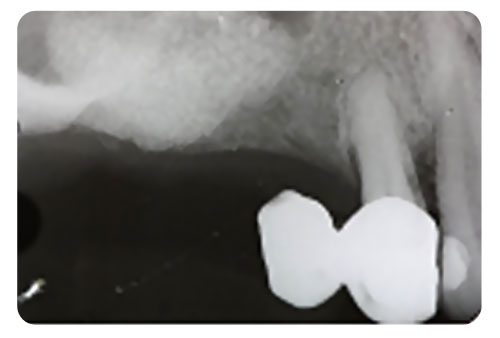

Antes de extrair um dente, seu dentista fará uma revisão completa no seu histórico médico e dentário e providenciará as radiografias necessárias.

As radiografias revelam o comprimento, formato e posição do dente e osso adjacente. Com base nessas informações, seu dentista poderá avaliar o grau de dificuldade do procedimento e decidir se deverá encaminhá-lo para um especialista, no caso, um cirurgião-dentista.